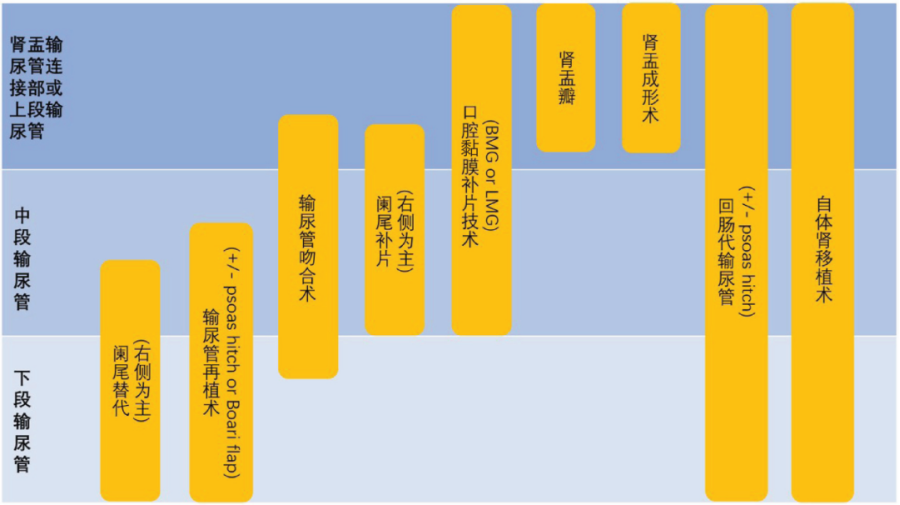

3.开放手术治疗

(1)输尿管狭窄段切除吻合术

适用于狭窄段较长、腔内治疗效果不佳的患者。切除狭窄段后,将输尿管断端进行吻合。

(2)输尿管膀胱再植术

用于输尿管膀胱连接部狭窄的治疗,将输尿管重新植入膀胱。

(3)肠代输尿管术

对于长段输尿管狭窄或多次手术失败的患者,可采用肠道替代输尿管。

(2)开放手术

根据狭窄的部位和程度选择合适的手术切口,如腰部切口、下腹部切口等。暴露输尿管狭窄段后,进行切除吻合、再植或替代等手术。